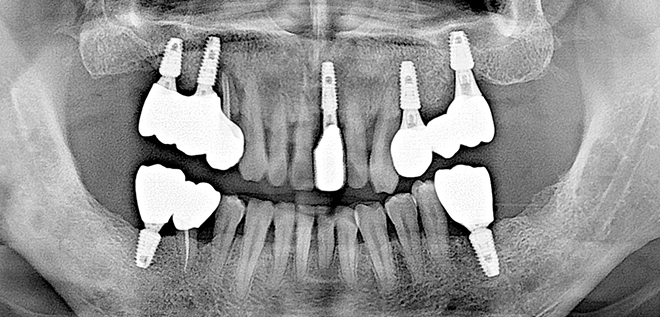

Before & After

어려운 임플란트 시술도

남양바른탑에서는 가능합니다.